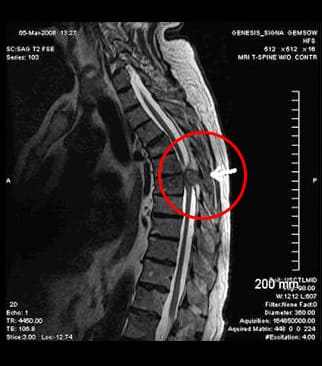

El ECG mostró que mi corazón estaba bien. En el hospital me realizaron un examen completo y me diagnosticaron osteocondrosis de la región torácica. ¡No me lo esperaba! Practico deportes, hago yoga y duermo en un colchón ortopédico toda mi vida. Todo en vano...